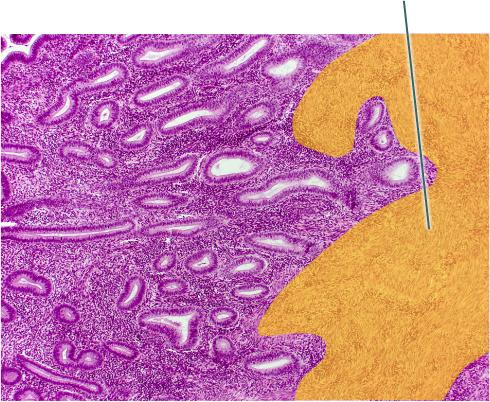

Identify the highlighted structure.

Corpus Cavernosum

Identify the highlighted structure.

Ductus Deferens

Identify the highlighted structure.

Epididymis

Identify the highlighted structure.

Glans Penis

Identify the highlighted structures.

Labia Majora